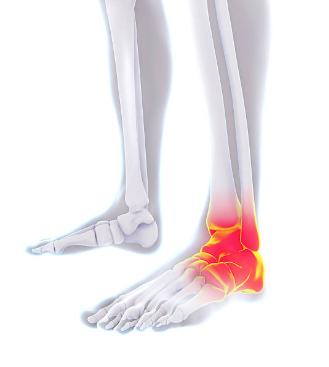

3. 골절

발목 골절은 발목 뼈 중 하나 이상이 부러진 경우를 말합니다. 이는 추락, 사고 또는 스포츠 부상과 같은 다양한 이유로 발생할 수 있습니다.